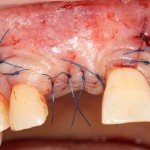

Во влажном состоянии она эластична и податлива, поэтому нет необходимости использовать пины или винты:

ну и, швы: